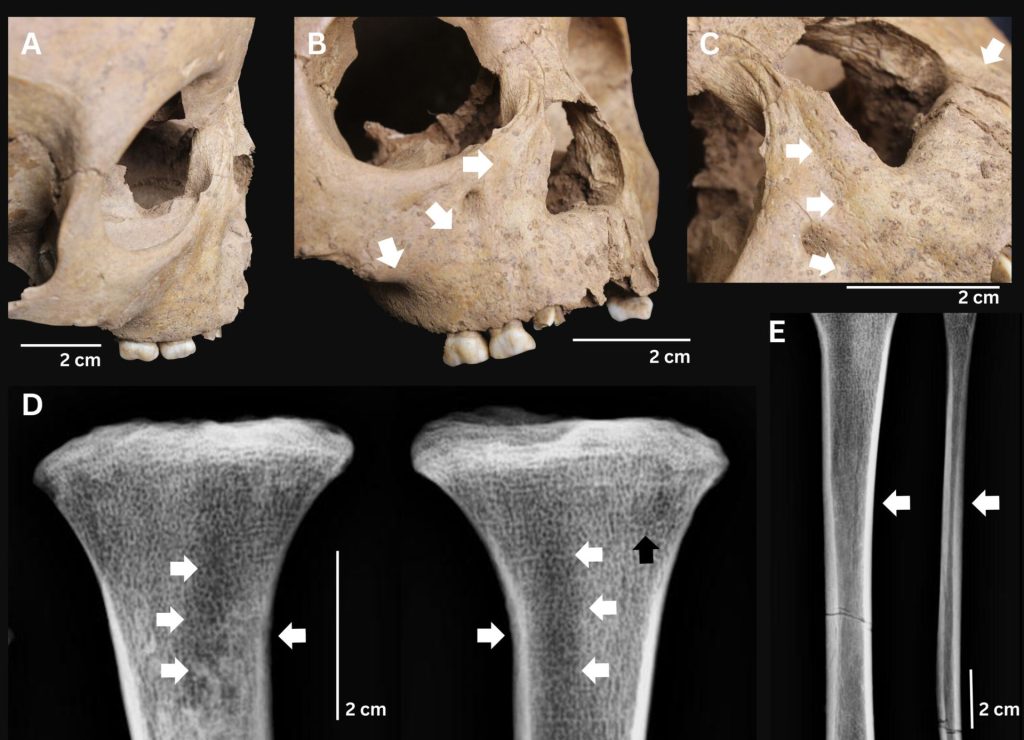

Noile cercetări arată că trei copii din Epoca de Piatră, descoperiți în Vietnam, sufereau de o boală bacteriană debilitantă, înrudită cu sifilisul. Această boală a lăsat urme vizibile pe oasele și dinții copiilor, oferind o perspectivă nouă asupra modului în care se răspândeau aceste afecțiuni în trecut. Analizele au fost efectuate asupra unor schelete descoperite în două situri neolitice, datând de acum 4.100-3.300 de ani.

Boala depistată este o formă de treponematoză congenitală, cauzată de bacteria Treponema pallidum. Această bacterie are mai multe subspecii, printre care sifilisul, bejelul și framboesia. Dinții copiilor prezintă deformări și un aspect deteriorat, sugerând suferința îndurată de aceștia. Majoritatea cazurilor au fost identificate la copii, ceea ce indică o posibilitate ridicată de transmitere congenitală, infirmând ipoteza răspândirii exclusive pe cale sexuală.

Un studiu anterior realizat în Vietnam, la situl Man Bac, a indicat că peste 10% dintre indivizii analizați prezentau semne ale bolii, majoritatea fiind copii și adolescenți. Noul studiu a analizat 304 indivizi din 16 situri vietnameze, datând de acum 10.000-1.000 de ani. În aceste situri au fost identificați trei copii afectați de boală, cu semne evidente în dinți.